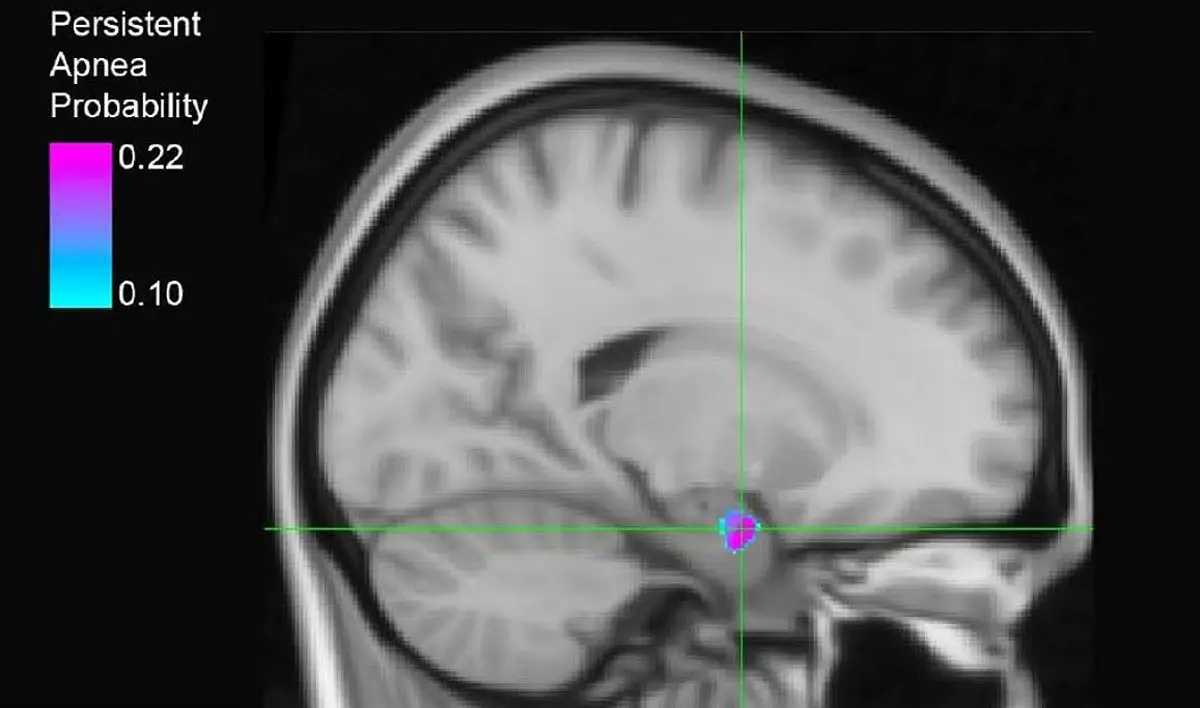

研究人员在杏仁核中发现了一个对癫痫发作后呼吸衰竭至关重要的部位。紫色和蓝色区域代表了与持续性呼吸暂停有关的区域的概率图,该图基于 20 名未受控制的癫痫患者的数据。资料来源:爱荷华大学 Dlouhy 实验室